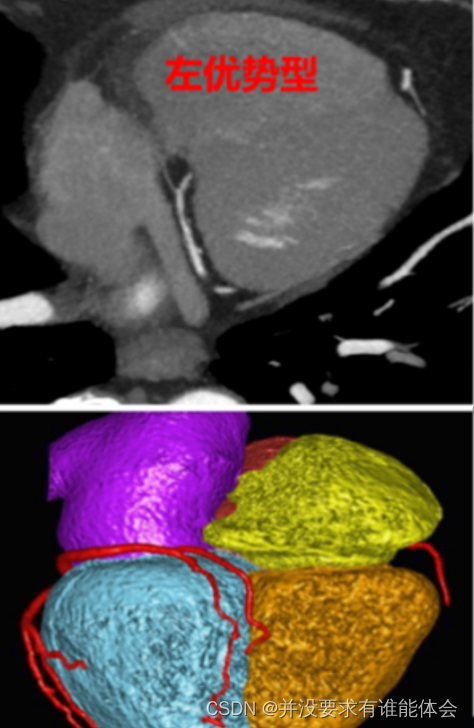

冠脉解剖-优势性

根据后降支和左室后支供应左心室后壁决定优势型,将冠状动脉分为以下3型:

1.右冠优於型:大约占85% 左右,后降支和左室后支起自右冠状动脉;左冠仅达左心室侧缘的左心室后壁

2.均街型:可见于7%病例,通常右元脉供应后降支,回旋支供应左室后支

3.左冠优势型:约8%病例,左旋支达右心室后壁,后降支和左室后支起自左回旋支,而冠仅达右心室右侧缘的右心室后壁